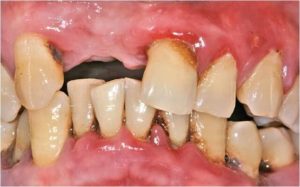

Вид больных и протезированых зубов, вы хотите себе такие зубы уже в молодом возрасте.

Заболевание пародонта – ответ организма на бактериальную инвазию

- Нарушение гигиены